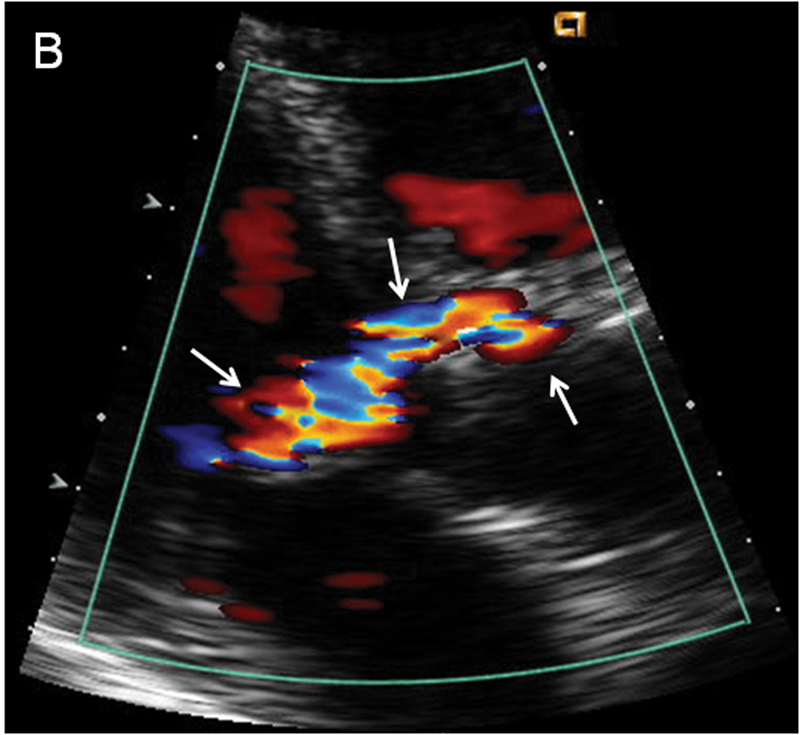

فحوصات تشخيصية لبعض امراض القلب والشرايين التاجية